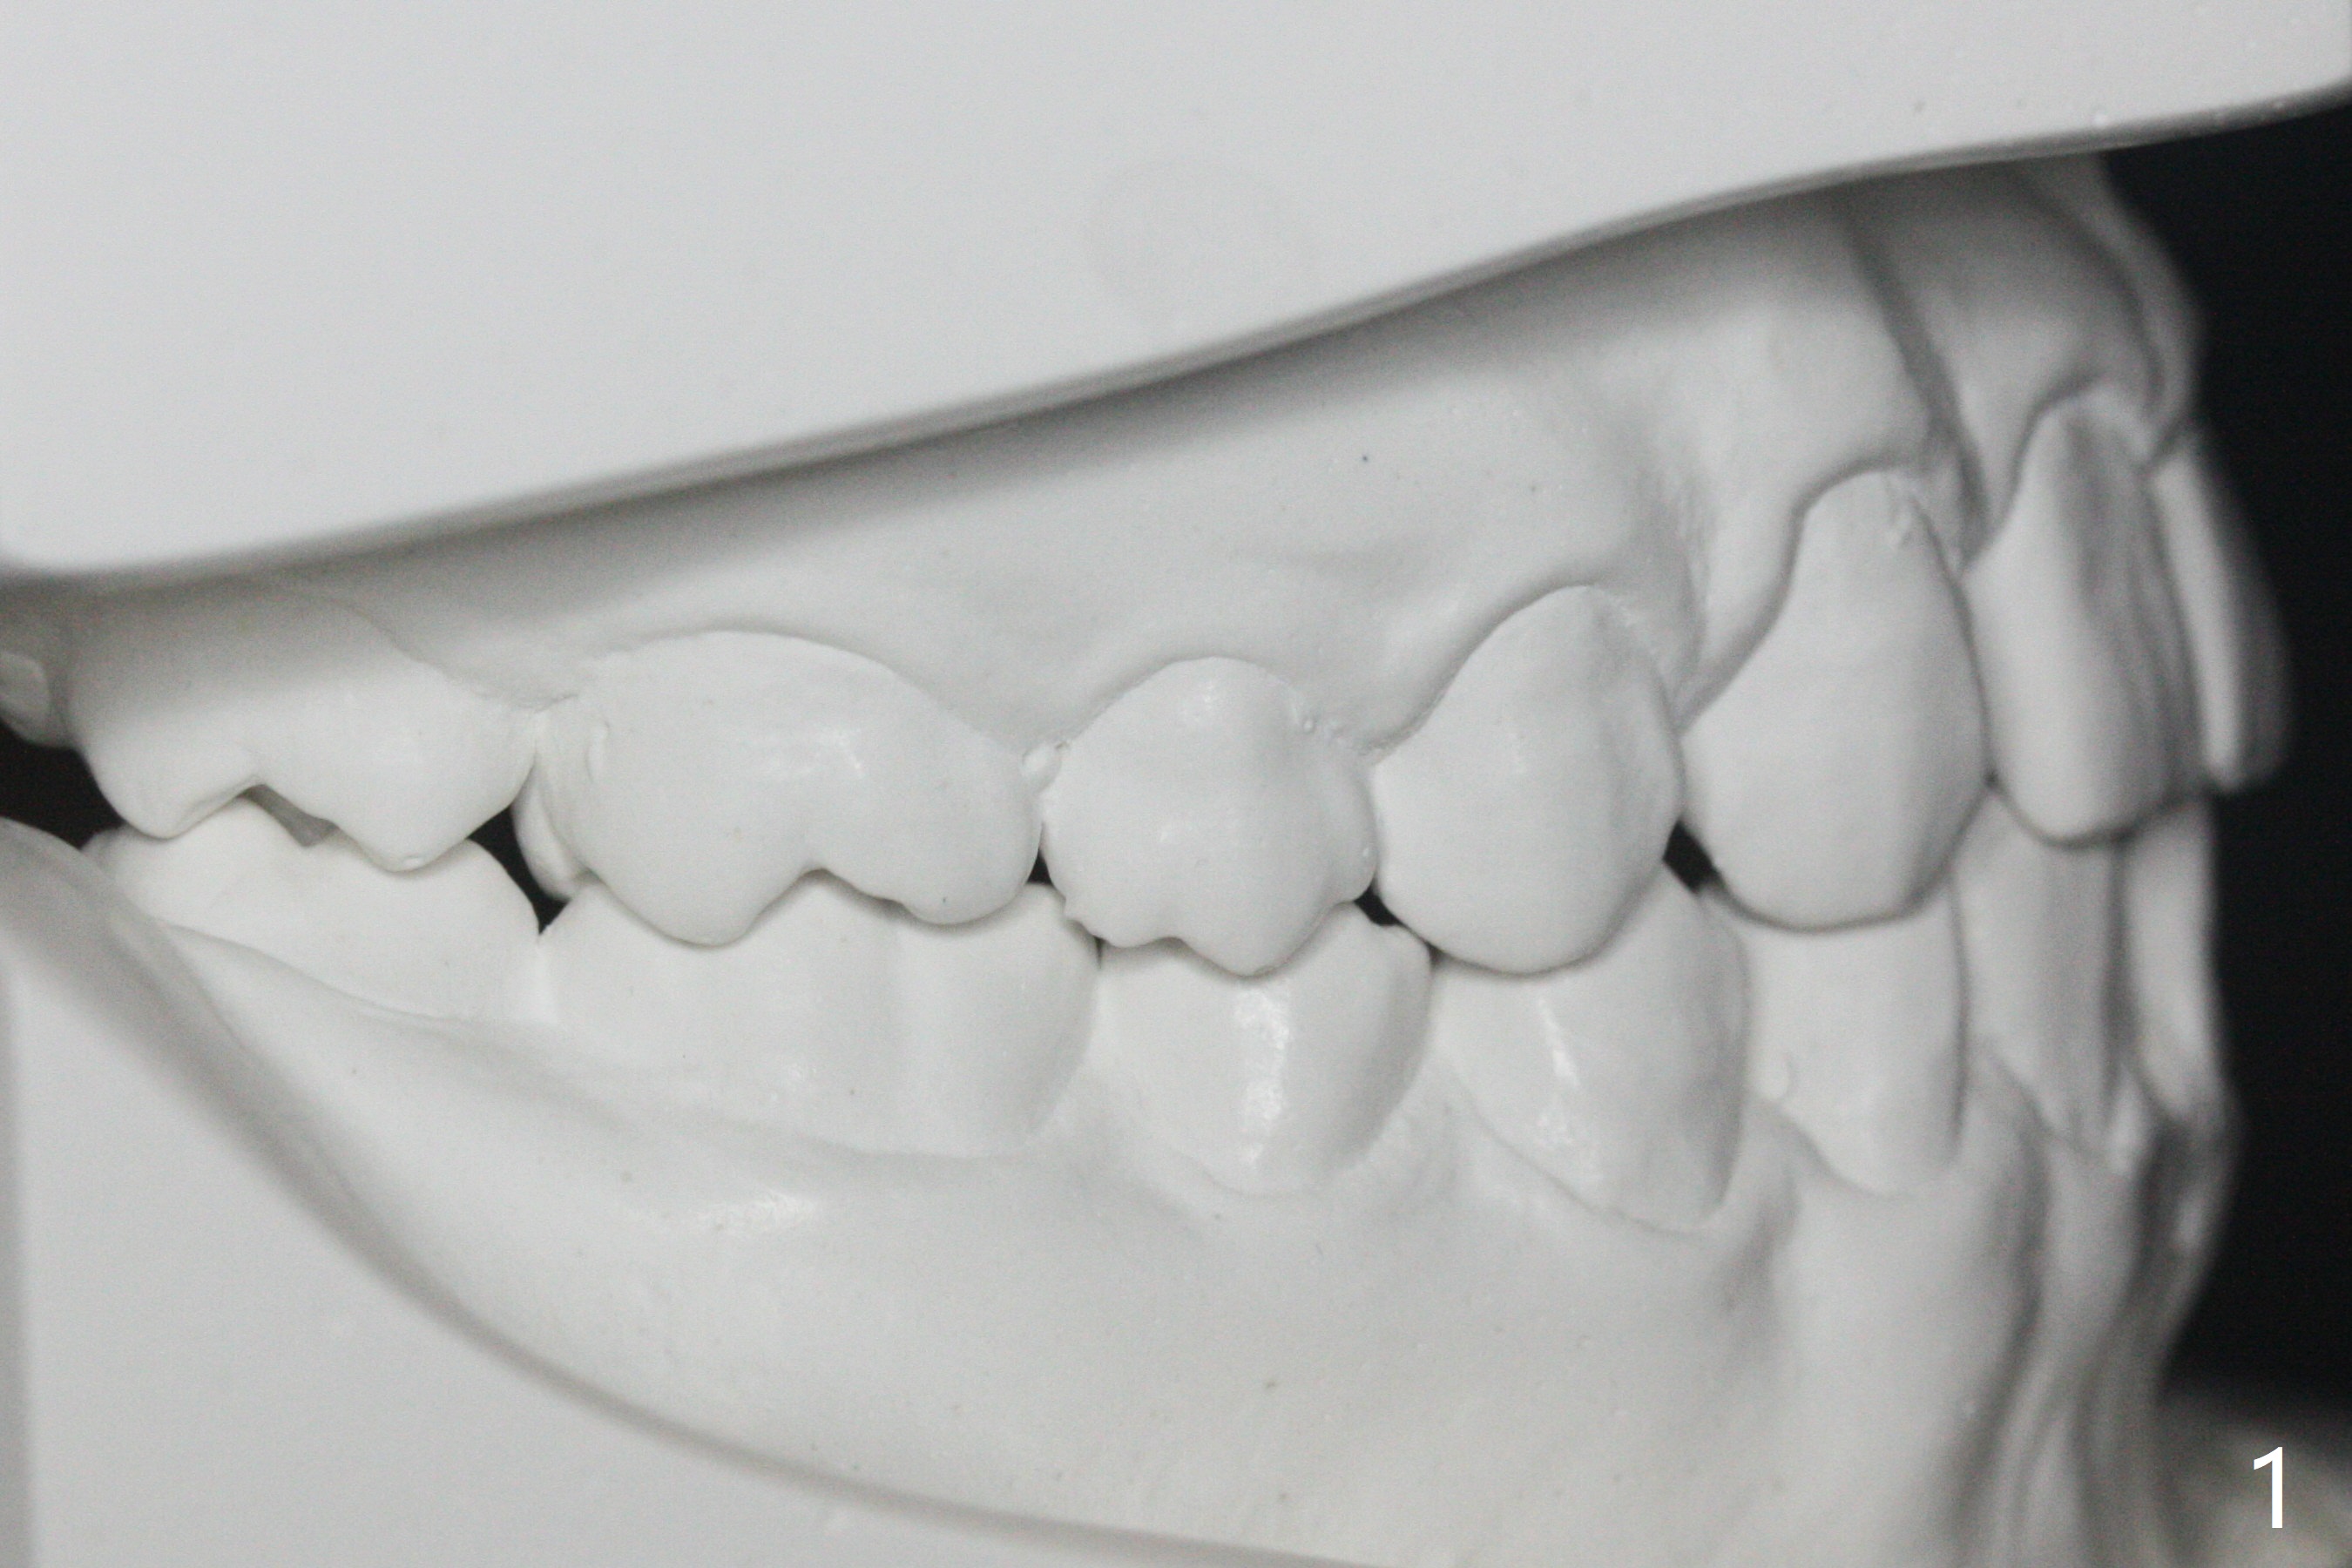

Bracketing for Congenital Missing Lateral